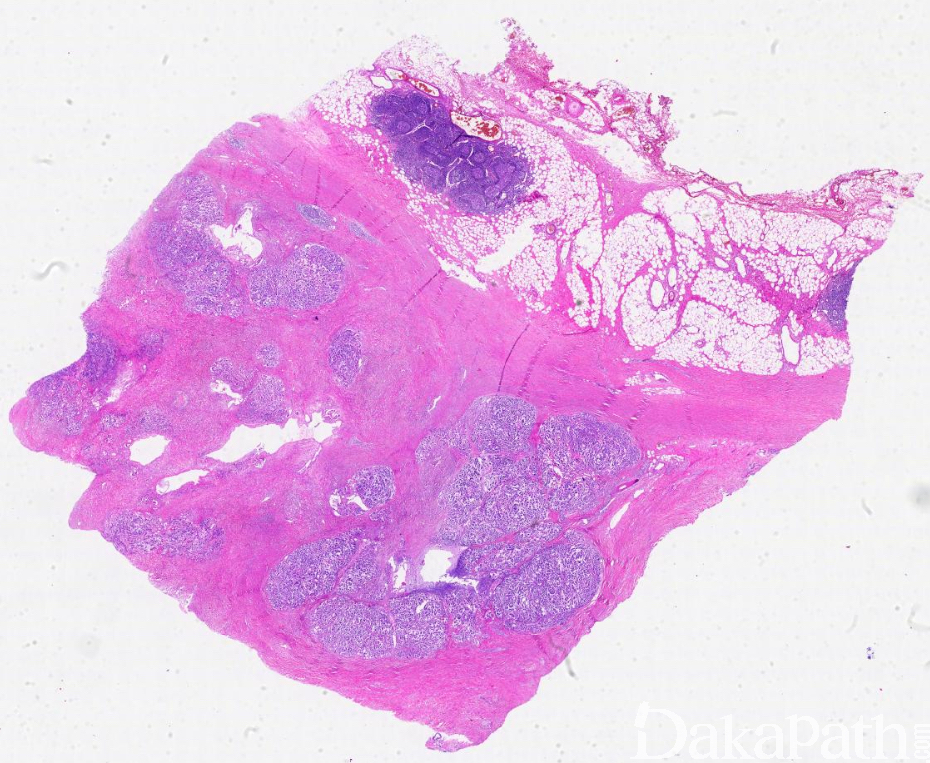

- 细胞丰富,肿瘤细胞与间质比例高,肿瘤细胞被纤细的纤维间隔带分开呈结节状,但无促纤维增生间质,可见坏死,肿瘤细胞巢周围有许多小血管。

- 肿瘤细胞在腺泡内形成筛状结构,或实性排列,无管腔形成,细胞核位于基底,无极向,形成栅栏状围绕血管排列,有时可见小梁状、脑回状、微囊等多种结构;

- 细胞形态多样,常由多种细胞组成,腺泡型细胞胞浆顶端为嗜酸性颗粒状,核偏位,圆形或卵圆形,异型性不大,有明显的单个核仁,核分裂多少不等。部分细胞可见胞质单个或多个空泡;还可见透明细胞、非特异性腺细胞(细胞界限不清,核中位)。